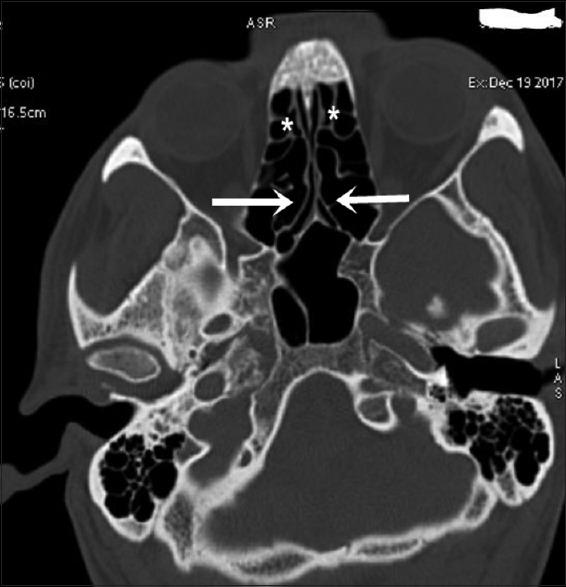

Among 250 study population, 100 were females and 150 males. Among these 423 cases of anatomical variants were observed. The most common anatomical variants were pneumatization of the middle nasal turbinates 30.73%. This is followed by agger nasi cells 21.64%, Haller's cells 22.91%, septal deviation 21.91%, and sphenoid sinus septation (20.18%).

CT is the gold standard in the radiologic investigation of the paranasal sinuses, sinonasal lesions, and inflammatory disease or pre- and post-surgical assessment. It has the capability of disclosing in greatest detail any anatomical variations, which could be causing or precipitating the sinusitis.